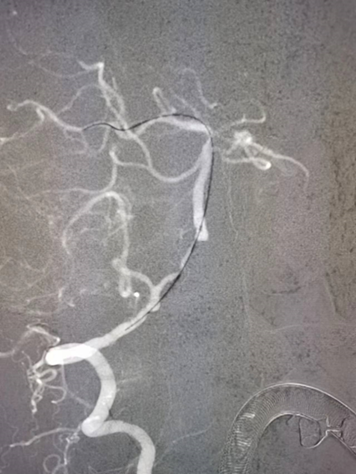

治疗中影像

病变情况分析:右桡动脉穿刺,置6F桡动脉鞘管,5F多功能导管在泥鳅导丝辅助下脑血管造影提示:右椎动脉V4段重度狭窄(约90%)。

导丝怎么扩【载药时代 球扩天下】NOVA DES®颅内药物洗脱支架在椎动脉颅内段重度狭窄的应用二例_https://www.jmylbn.com_新闻资讯_第31张

导丝怎么扩【载药时代 球扩天下】NOVA DES®颅内药物洗脱支架在椎动脉颅内段重度狭窄的应用二例_https://www.jmylbn.com_新闻资讯_第32张

泥鳅导丝携5F 115cm颅内支撑导管,至右椎动脉V2段。

在颅内支撑导管支撑下,将0.014'' 300cm微导丝,通过狭窄节段将其放置在基底动脉中段。将2.0mm*10mm球囊打起预扩狭窄部位,然后更换赛诺神畅 颅内药物洗脱支架NOVA DES® 2.5*10mm延微导丝顺利通过狭窄节段,再次造影见定位准确,缓慢扩张球囊释放支架。

导丝怎么扩【载药时代 球扩天下】NOVA DES®颅内药物洗脱支架在椎动脉颅内段重度狭窄的应用二例_https://www.jmylbn.com_新闻资讯_第33张